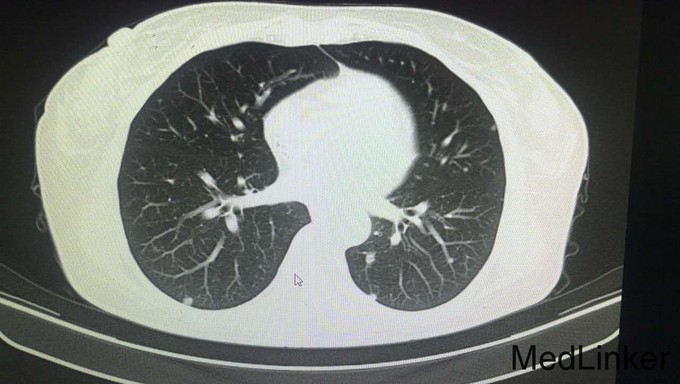

查体:腹平软,全腹部未扪及明显包块,全腹无压痛、反跳痛,右侧上中腹部可见一长约12cm的手术瘢痕,愈合良好,肝脾肋下未触及,墨菲氏征阴性,移动性浊音阴性,肠鸣音正常,无血管杂音。双肺呼吸音清,未闻及干湿性啰音,心脏听诊律齐,各瓣膜区未闻及明显病理性杂音。四肢查体无明显异常。 辅查:术后病理示:右半结肠中分化腺癌,部分为粘液腺癌,浸润肠壁全层,并侵犯神经组织,胰腺旁淋巴结见癌组织浸润并侵犯神经组织。2015年4月全身PET/CT检查示:右半结肠吻合口未见占位,纵膈1L组、肝门、腹膜后、右侧结肠旁沟淋巴结转移瘤,肝内转移瘤,胰头下方软组织转移瘤,双肺多发小结节,不排除转移瘤。2015年6月复查CEA:1353ng/mL,CA199:9674u/mL(较前明显升高)。其余重要影像学检查如下图所示: